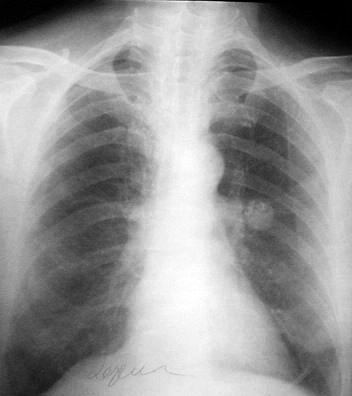

Opacitate bine delimitată, mediopulmonar stânga cu zone de calcificare - tumoră benignă